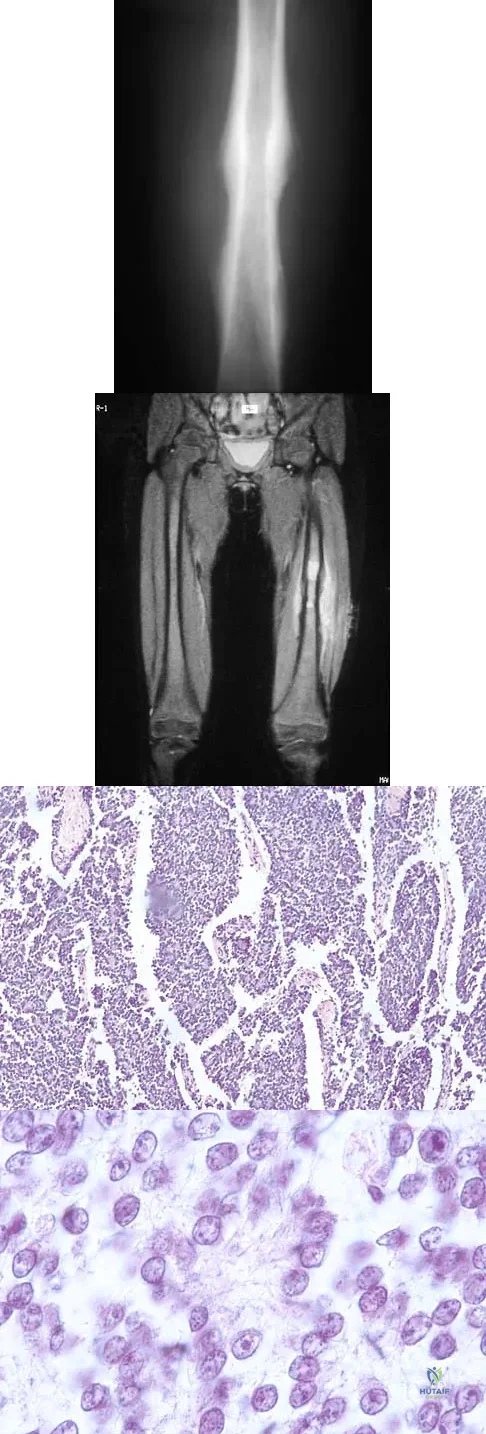

A 16-year-old boy has had thigh pain for the past several months. He denies any history of trauma. Examination reveals a large, deeply fixed, soft-tissue mass in the thigh. Laboratory results show an elevated erythrocyte sedimentation rate (ESR) and leukocytosis. A plain radiograph and MRI scan are shown in Figures 1a and 1b. Biopsy specimens are shown in Figures 1c and 1d. What is the most likely diagnosis?

Explanation